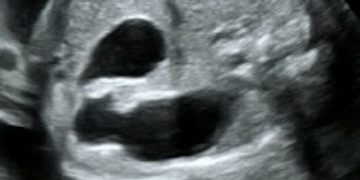

Guida al Counselling di Maggio 2025: patologie cistiche della fossa cranica posteriore

Cari colleghi, vi presentiamo la guida al counseling di Maggio 2025 sulla Patologia cistica della fossa cranica posteriore. Potrete scaricarla cliccando sul link. Grazie a Laura Sarno! ...